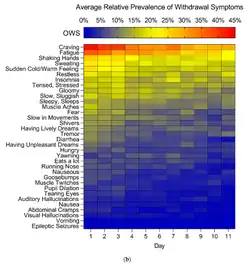

Physical dependence develops quickly and is highly addictive. It shares some similarities, when suddenly discontinued, with the withdrawal symptoms of gabapentinoids phenibut and baclofen due to the activation of the GABAB receptor. It features a typical depressant withdrawal syndrome that mimics alcohol withdrawal.[122] Symptoms include delirium, tremor, anxiety, tachycardia, insomnia, hypertension, confusion, sweating, severe agitation which may require restraint,[123] auditory and visual hallucinations, and possibly death from tonic-clonic seizures.[123][124][122][125][126][127]

Physical or physiological dependence does occur during the long-term use of gabapentinoids.[66] Following abrupt or rapid discontinuation of pregabalin and gabapentin, people report withdrawal symptoms like insomnia, headache, nausea, diarrhea, flu-like symptoms, anxiety, depression, pain, hyperhidrosis, seizures, psychomotor agitation, confusion, disorientation, and gastrointestinal complaints.[67][68] Acute withdrawal from baclofen and phenibut may also cause auditory and visual hallucinations, as well as acute psychosis.[69][70] Baclofen withdrawal can be more intense if it is administered intrathecally or for long periods of time. If baclofen or phenibut is used for long periods of time, it can resemble intense benzodiazepine, GHB, or alcohol withdrawal. To minimize withdrawal symptoms, baclofen or phenibut should be tapered down slowly. Abrupt withdrawal from phenibut or baclofen could possibly be life-threatening because of its mechanism of action. Abrupt withdrawal can cause rebound seizures and severe agitation.[71][70]